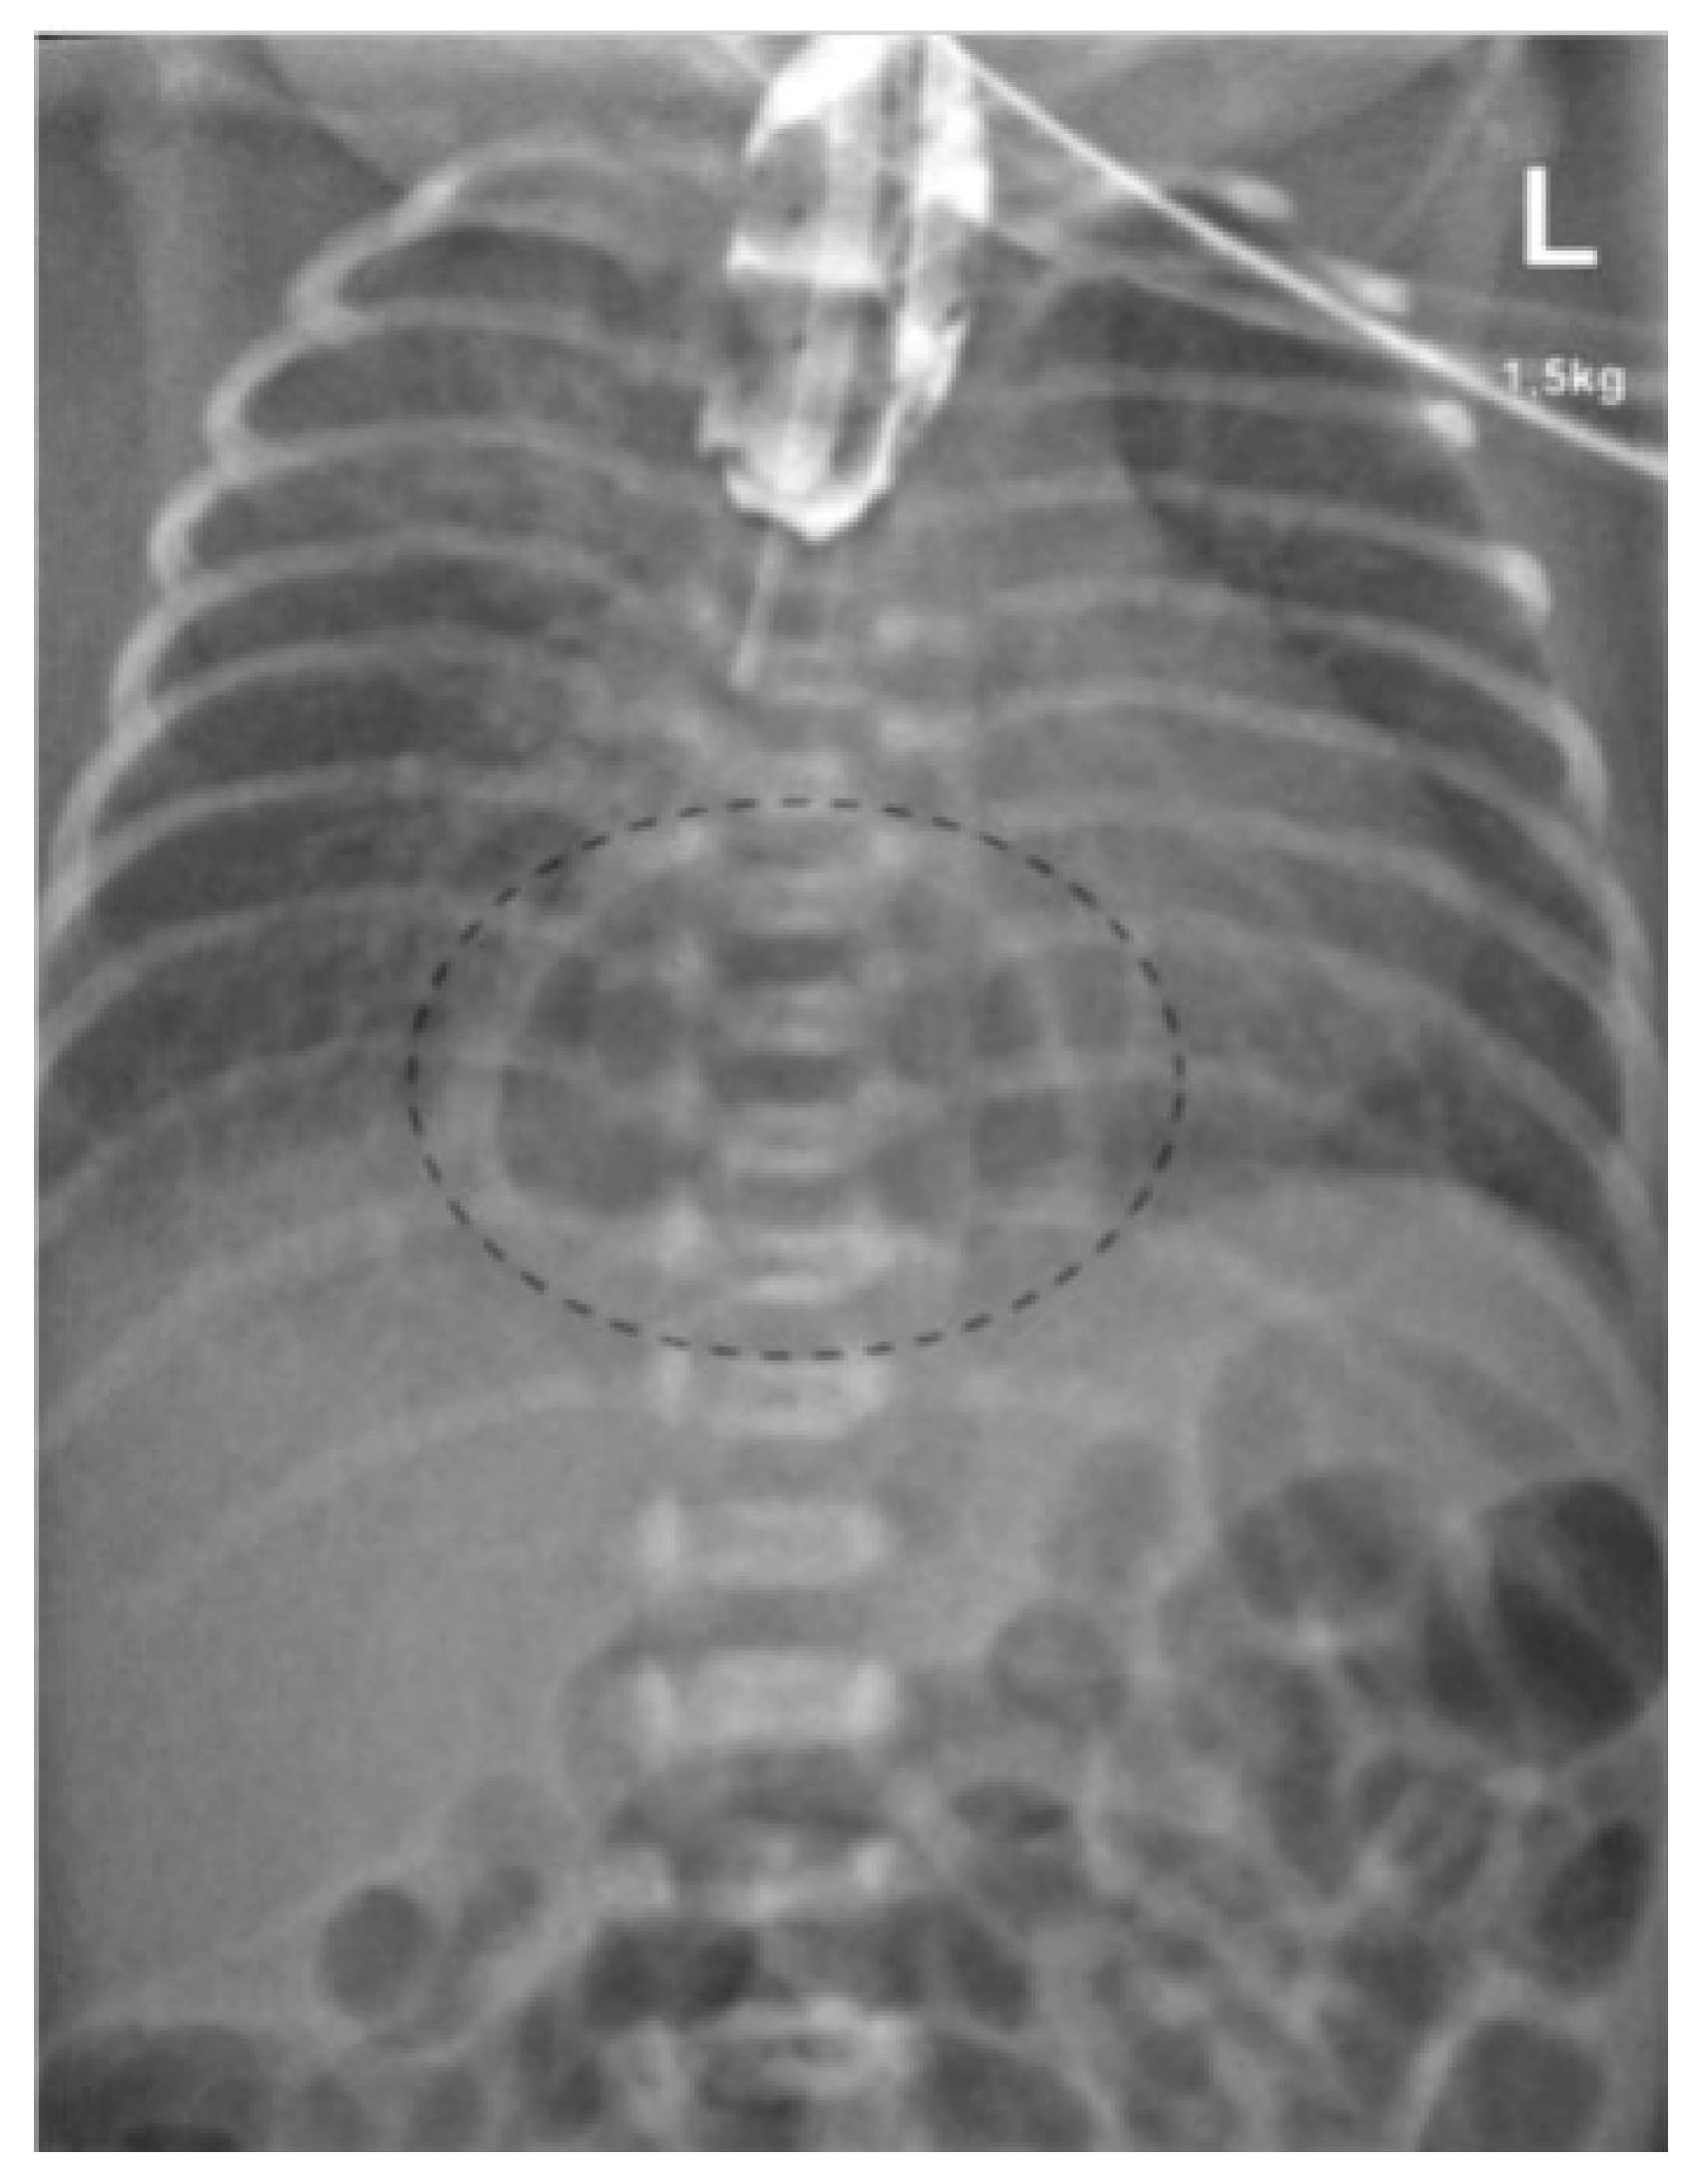

A 34-year-old woman, gravida 3, para 2, was referred to our hospital after the referring gynecologist had diagnosed significant polyhydramnios at 31 weeks of gestation. On arrival, the membranes ruptured prematurely without regular uterine contractions. To reduce the risk of a respiratory distress syndrome induction of fetal lung maturation was started (single course: 2 doses of Betamethason 12 mg i.m. 24 h apart) and tocolysis with a calcium antagonist was administrated. The fetal ultrasound performed on admission confirmed a massive polyhydramnios with a fluid collection in the neck (“pouch sign”) and no stomach in the abdomen, suggestive of esophageal atresia (Figure 1). Despite tocolysis the patient delivered vaginally a few hours later at 31 5/7 weeks of gestation.

Figure 1. (a) “Pouch sign”—Prevertebral fluid accumulation inside the region of the neck/mediastinum, possibly suggesting esophageal atresia in gestational week 31. (b) Fetal ultrasound showing the absence of the stomach intraabdominally in gestational week 31.